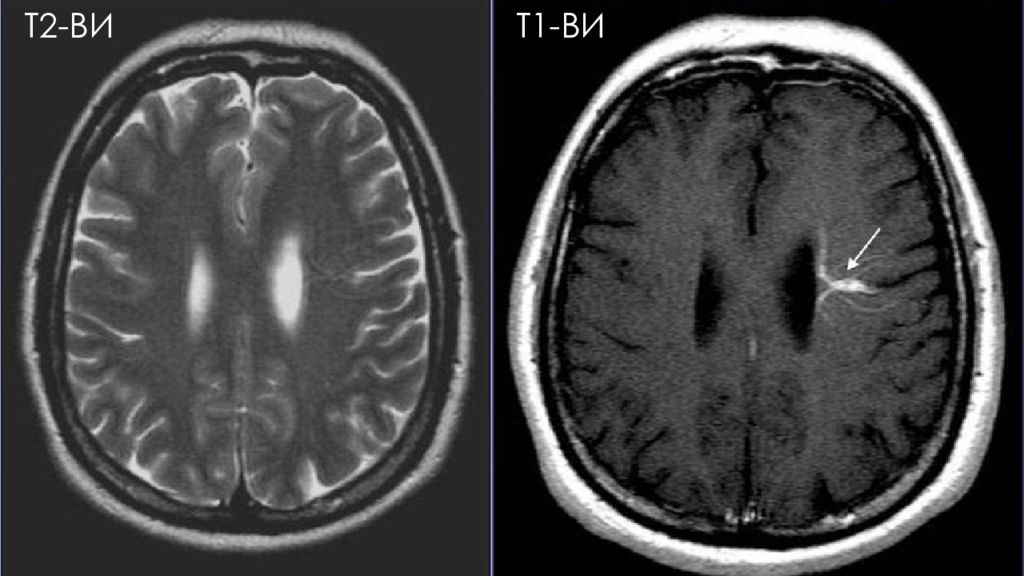

Т2-ВИ Т1-ВИ